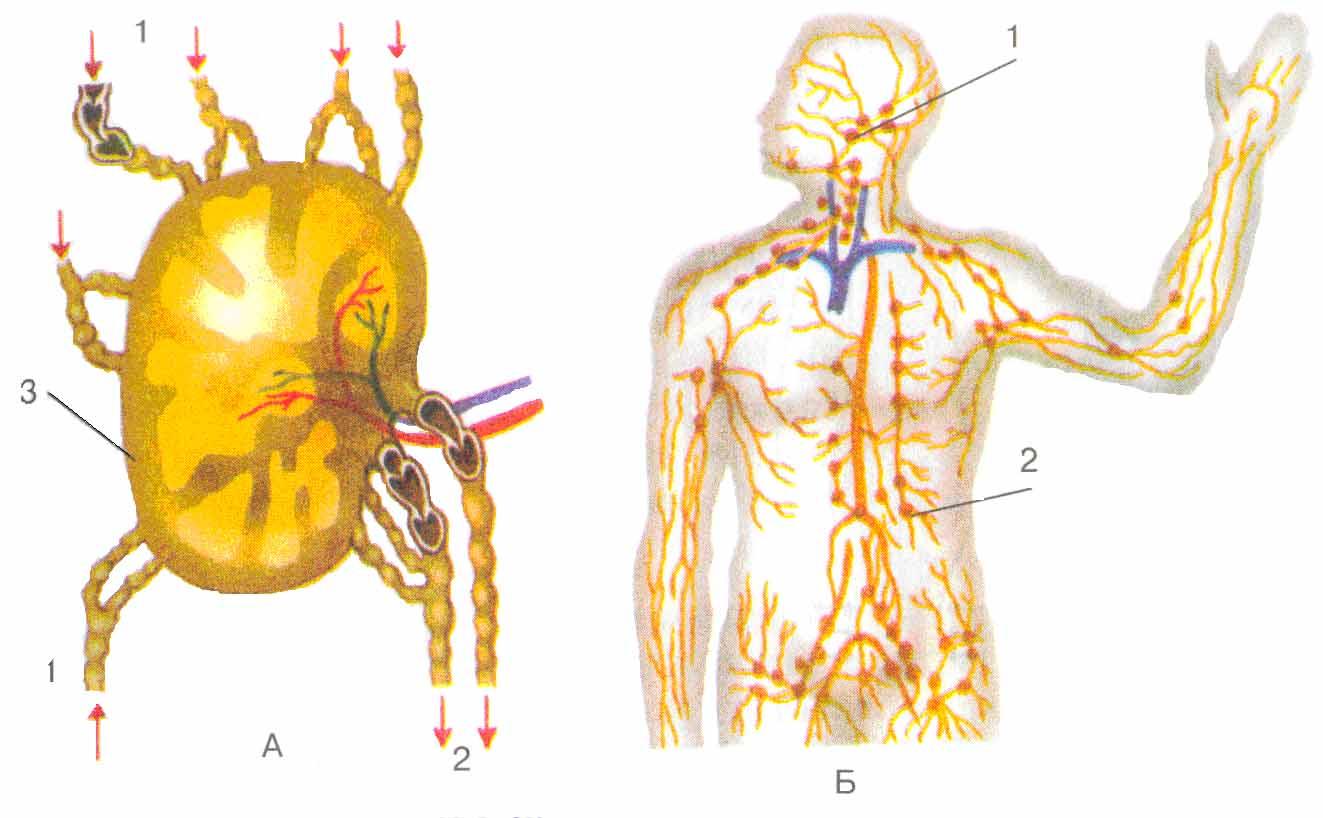

Изображения и схемы: как выглядит лимфа